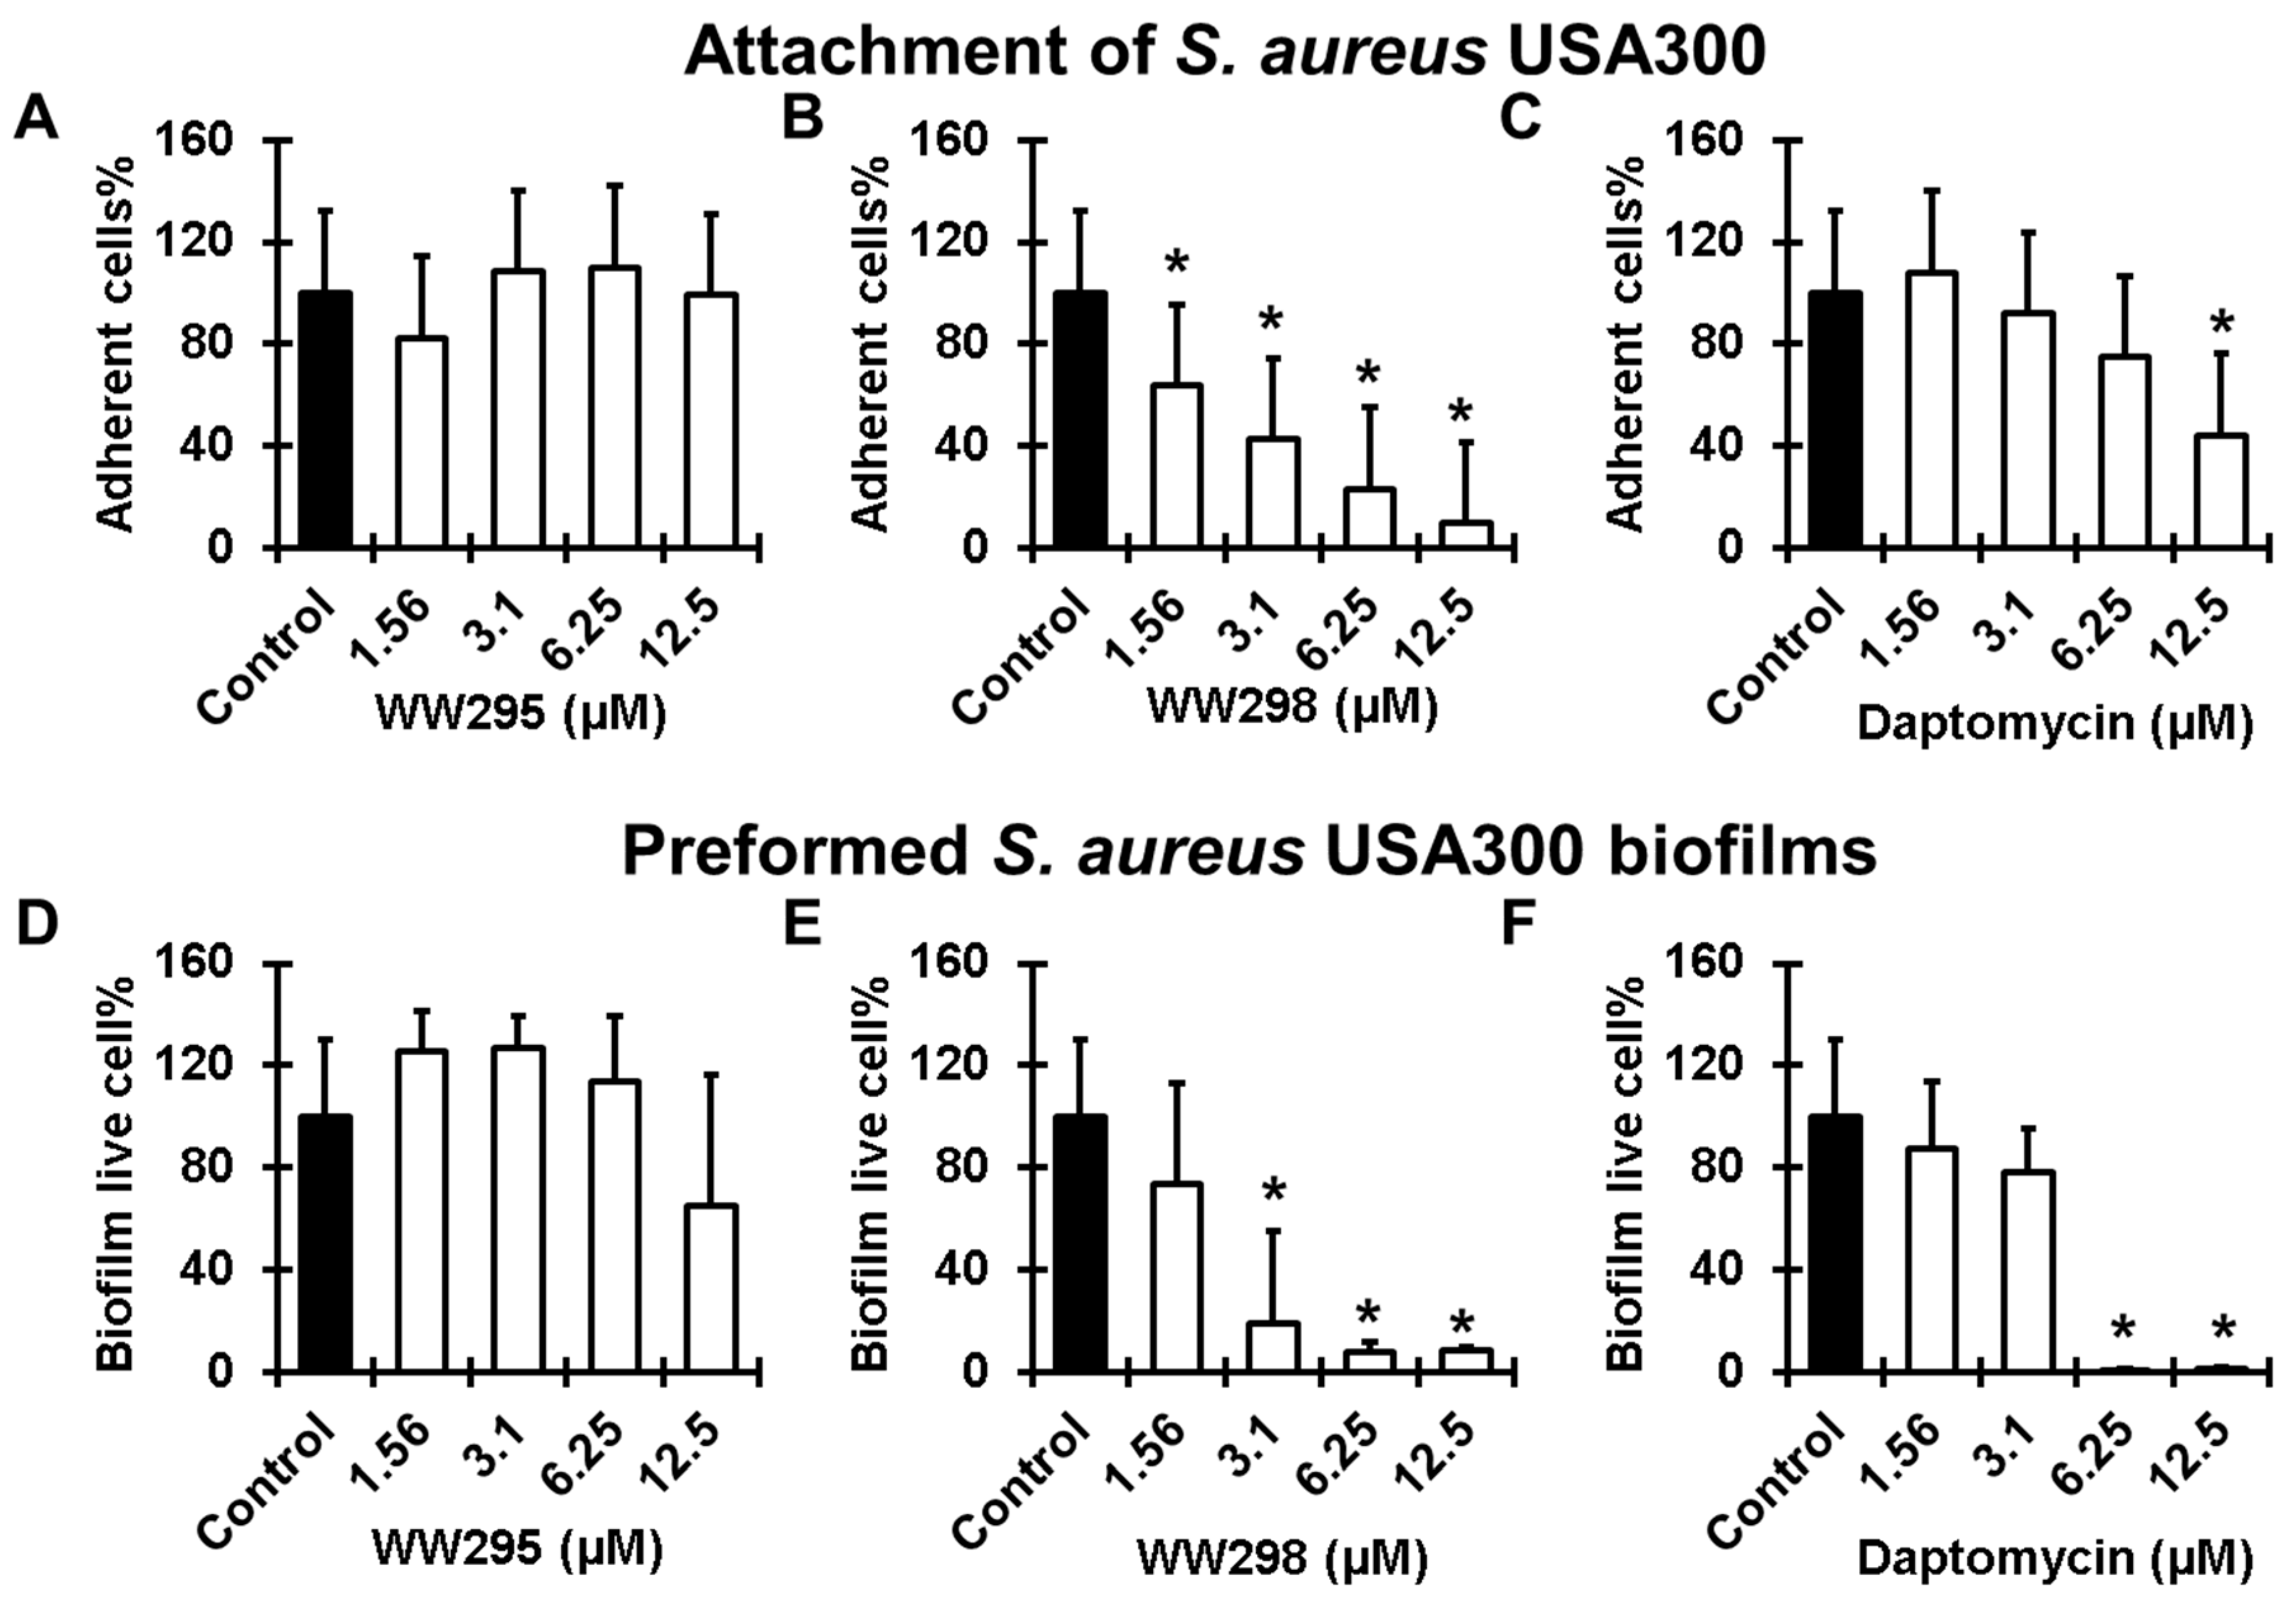

2.7. Antibiofilm Effects on MRSA

4.10. Peptide Effects on Biofilm Attachment

4.11. Antibiofilm Effects on 24 h Established Bacterial Biofilms

4.12. Confocal Microscopy Observation of Live and Dead Bacteria in Established Biofilms after Peptide Treatment